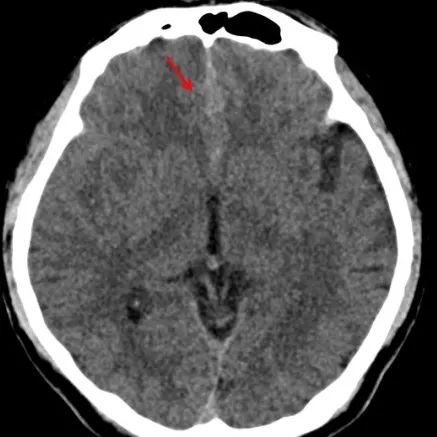

烟雾病和烟雾综合征

*仅供医学专业人士阅读参考烟雾病影像表现 本文首发:徐医附院影像科责任编辑:孙颖版权申明 本文转载 欢迎转发朋友圈- End -*医学界力求其发表内容在审核通过时的准确可靠,但并不对已发表内容的适时性,以及所引用资料(如有)的准确性和完整性等作出任何承诺和保证,亦不承担因该些内容已过时、所引用资料可能的不准确或不完整等情况引起的任何责任。请相关各方在采用或者以此作为决策依据时另行核查。...